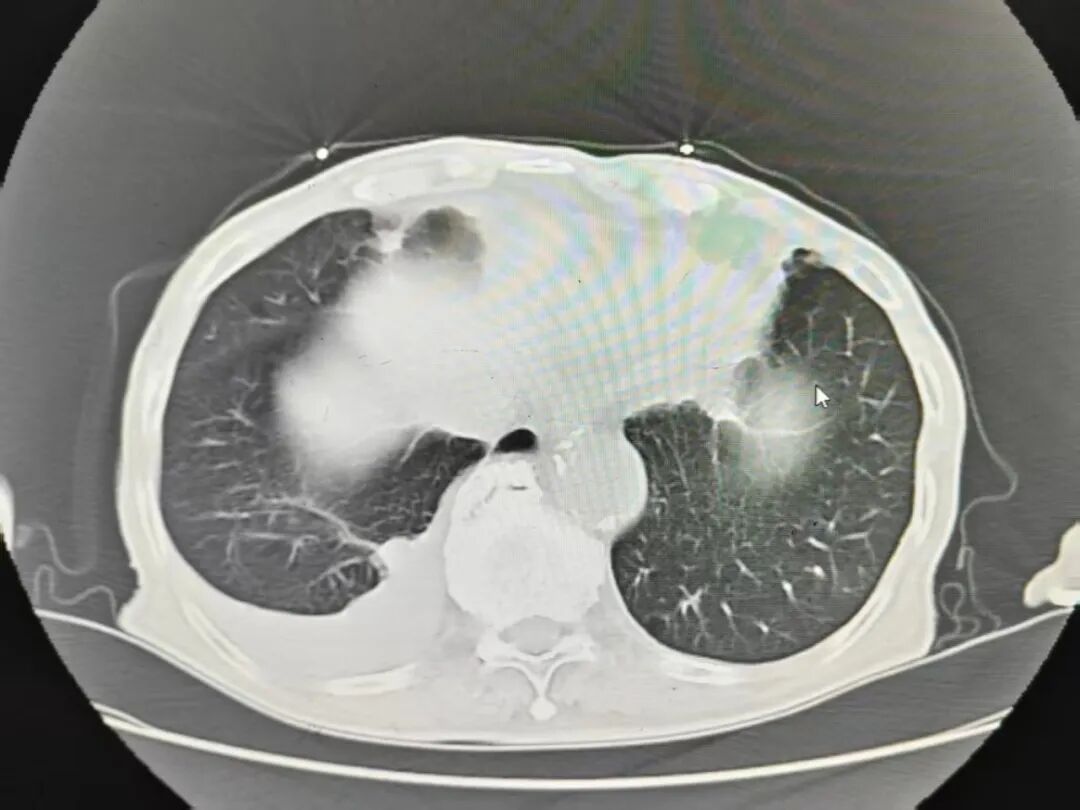

王爷爷在家人的陪同下,来到奉贤区中医医院急诊就诊。医生为他进行初步的检查,检查结果显示,王爷爷的心影增大,右侧有胸腔积液。

经过12天的系统治疗,王爷爷的症状显著改善:活动后偶尔有胸闷气短症状出现,比较之前好转了很多,夜间再也没有因为胸闷憋醒需要坐起来的情况,一阵阵的心慌消失了,咳嗽咳痰也没有了,双下肢水肿完全消退。复查的心衰指标、心电图、胸腔积液情况都明显好转。